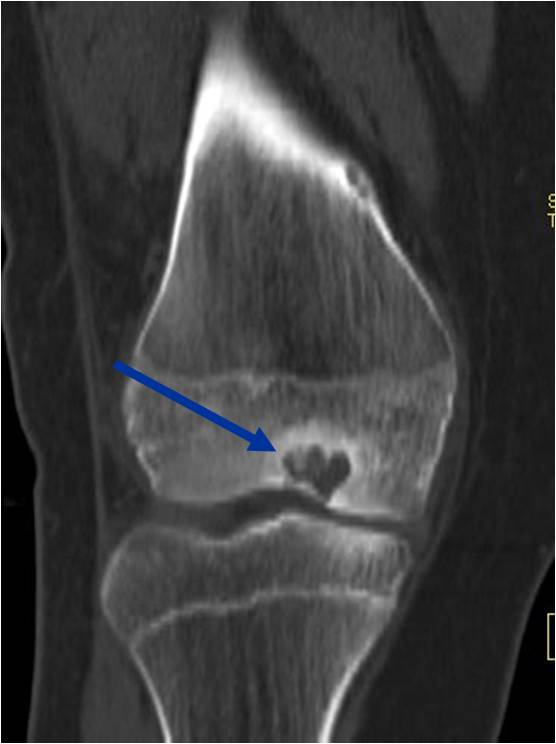

- (CT appearance)

- Most useful for detecting subtle mineralization not apparent on X-rays

- Useful for identifying intact periosteum around any expansile soft tissue component

- surrounding thin reactive shell of bone/mineralization (Egg Shell Rim of Calcification)

- helps place the tumor in a benign category

- helps evaluate:

- bony quality

- extent of bone and cortical destruction

- whether the subchondral plate of bone adjacent to the articular cartilage has been destroyed or is intact